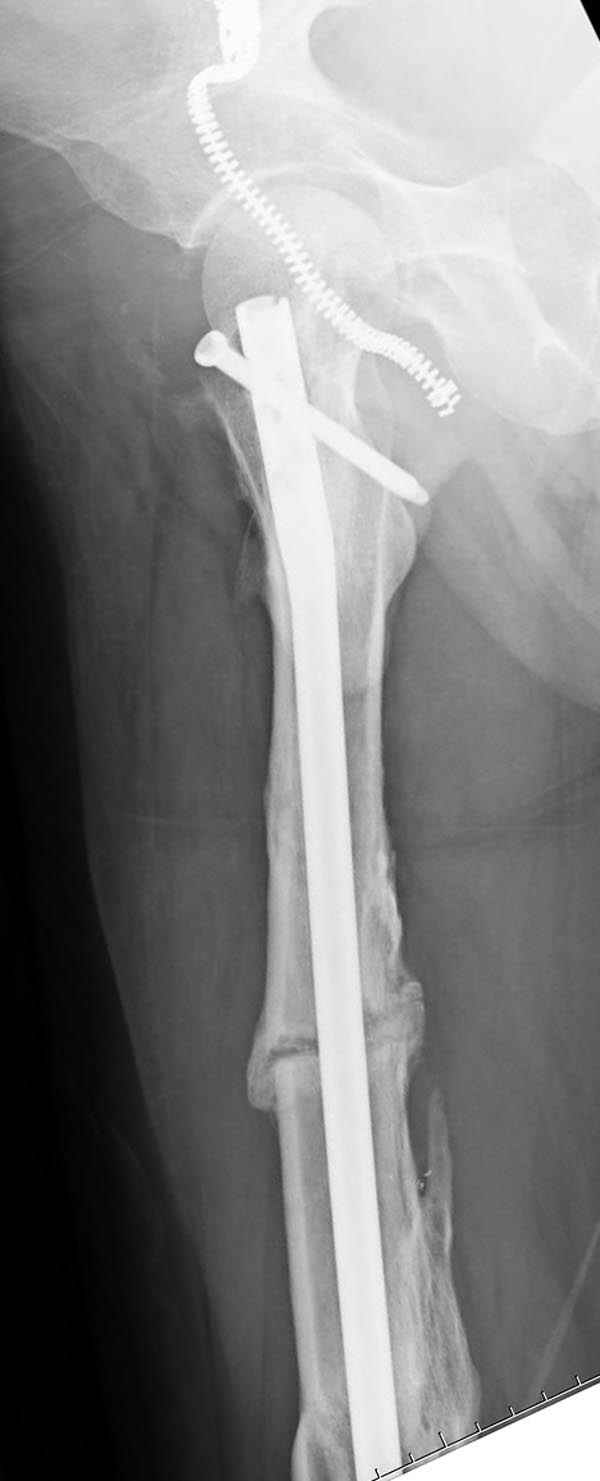

Представляю снимки больного с политравмой: леченного в другом мед.учреждении по поводу открытого перелома бедра, сперва аппаратом наружной фиксации, затем пластиной. Обратился к нам через 8 месяцев после удаления пластины с проблемой несросщего перелома бедренной кости, без клинических проявлении к инфицированию (не все снимки сохранены)

Рутинный интрамедуллярный остеосинтез с расверливанием и с фиксацией реконструктивным трокантерик штифтом (рис №1, №2),

если первые 4 месяца послеоперационного периода проходил без проблем, но на 5 месяце появились боли в дистальном отделе бедра и температура, т.е. симптомы медуллярного инфицирования (рис №3, №4).